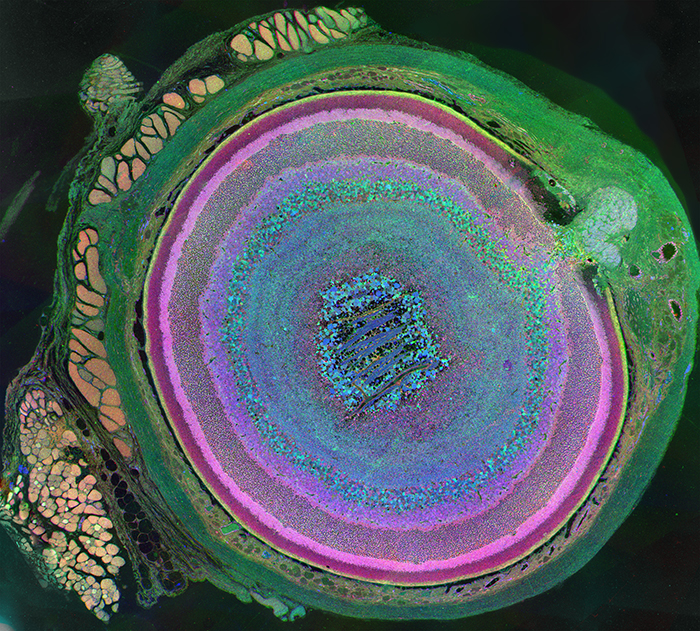

Remodeled Retina

Metabolomic Eye Wins Science and Engineering Visualization Challenge